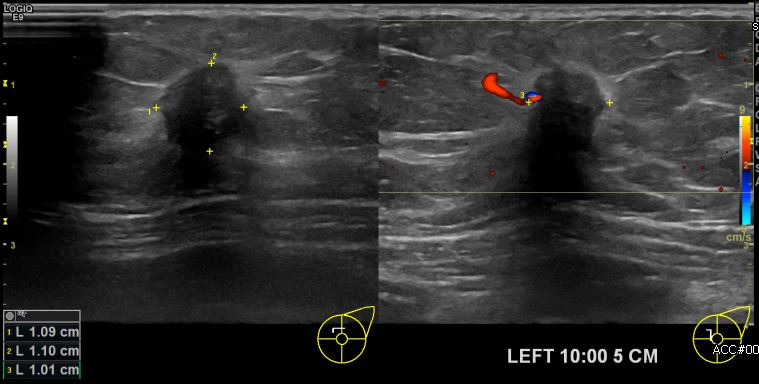

상기환자 건강검진상 이상 소견으로 내원하신 70대 여성분으로 좌측 10시 방향에서

5cm 떨어진 거리의 멍울 조직검사 시행하여 좌측 침윤성 유관암 진단 되었습니다.